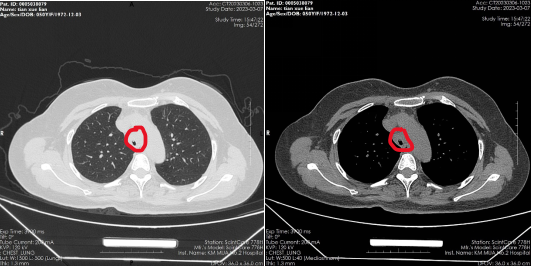

患者,女,50岁,因“外伤后呼吸困难2月”来到樱花动漫 全科医学科治疗。患者2月前因外伤致气管撕裂,在当地医院行气管修补术,术后出现进行性加重呼吸困难。患者来到我院住院后,稍微活动就会感到气促,已不能活动,肺功能显示重度阻塞性肺通气功能障碍,胸部CT显示气管下段重度狭窄,支气管镜检查显示气管下段距隆突2cm处重度瘢痕狭窄,最窄处仅4mm,随时都会发生窒息甚至猝死,手术迫在眉睫!

气管下段狭窄治疗前

气管下段狭窄激光治疗+Y型硅酮支架植入后